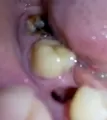

Здравствуйте. От 6-го нижнего зуба остался один корень. Зуб не болит, нервы удалены, каналы запломбированы. Зуб нужно удалить. Насколько сложна данная процедура и будут ли мне резать десну? Спасибо.

Добрый день! Если разрушение зуба не ниже основания десны и при этом каналы хорошо (!!!) пролечены (нет воспалительных процессов, грануляций), и ткани зуба плотные, то зуб можно восстановить культевой восстановительной вкладкой, а затем коронкой. Я вам рекомендую обратиться на прием к грамотному ортопеду для анализа состояния корня зуба. Если потребуется моя помощь , обращайтесь всегда рад вам помочь.